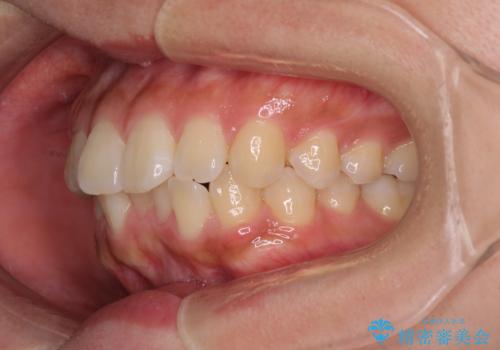

- 前歯の突出感を気にして来院された患者様です。

咬合力が非常に強く、咬合力で前歯が前方に押し広げられており、上下唇に閉じにくさが認められました。

上下左右の第一小臼歯4本を抜歯し、ワイヤー装置にて矯正治療を行うこととしました。

強い咬合力により前歯の隙間がなかなか閉じられず、治療期間は長いものとなりましたが、横顔の印象が大きく変わるほど口元の印象を改善することができました。